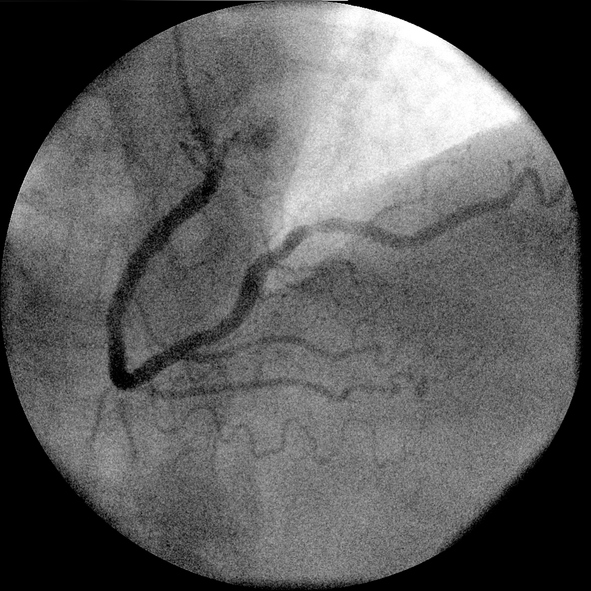

심혈관질환.jpg

[사진=게티이미지뱅크]